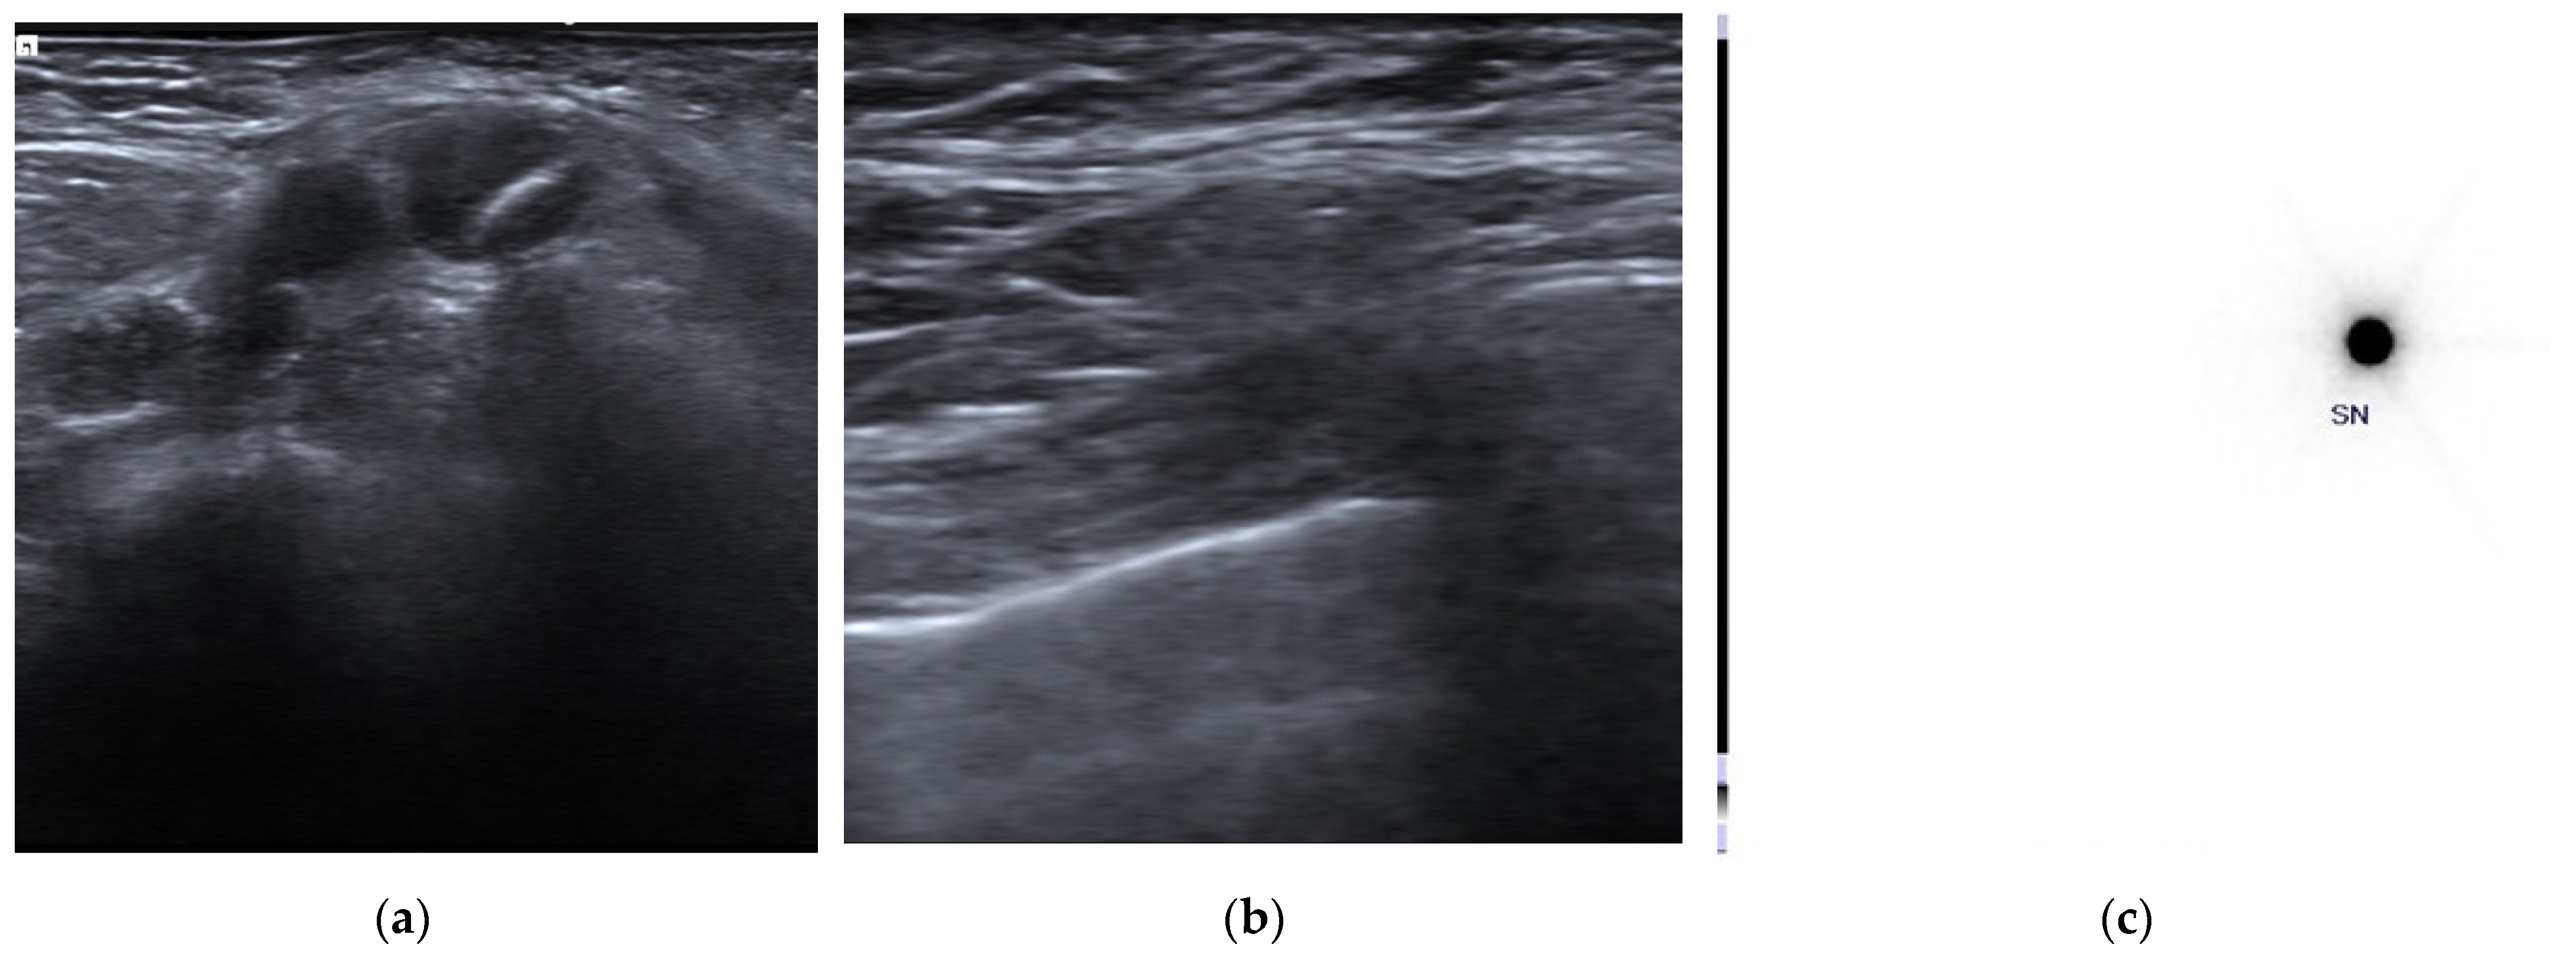

- Hellingman, D.; Donswijk, M.; Winter-Warnars, G.A.O.; De Koekkoek-Doll, P.; Pinas, M.; Namen, Y.B.-V.; Westerga, J.; Peeters, M.-J.T.F.D.V.; Kimmings, N.; Stokkel, M.P.M. Feasibility of radioguided occult lesion localization of clip-marked lymph nodes for tailored axillary treatment in breast cancer patients treated with neoadjuvant systemic therapy. EJNMMI Res. 2019, 9, 94. [Google Scholar] [CrossRef]